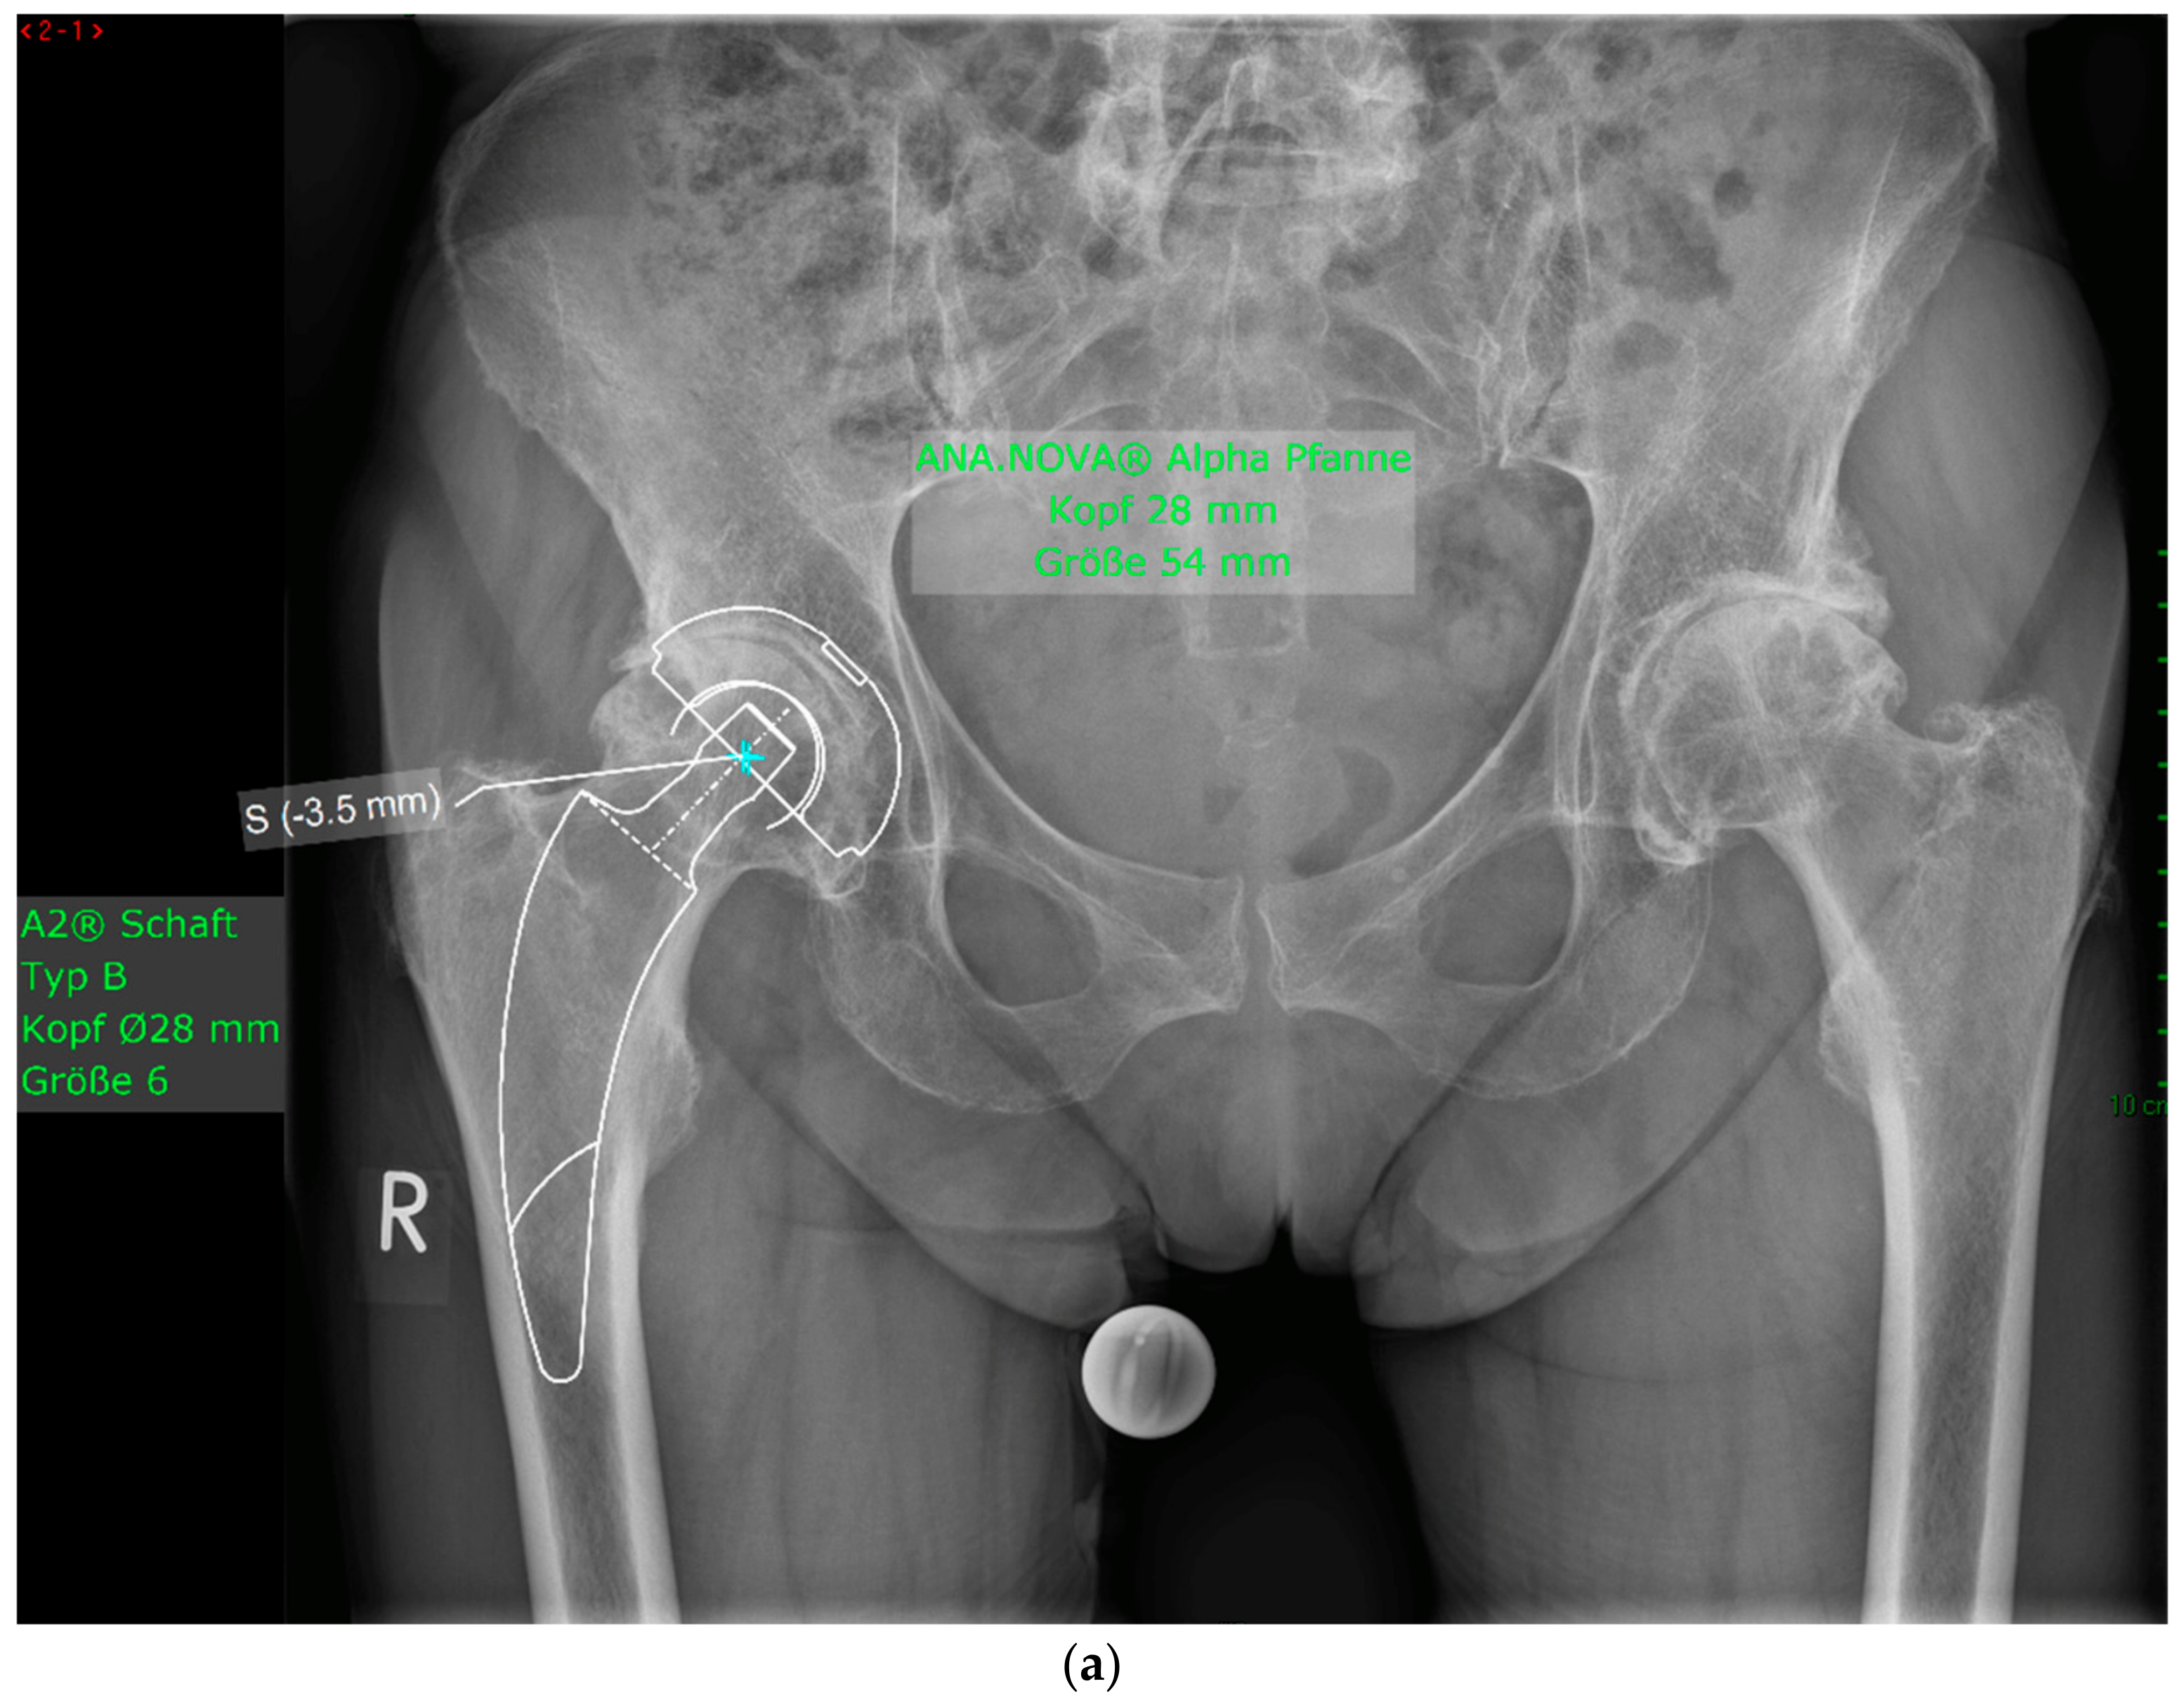

2. Materials and Methods